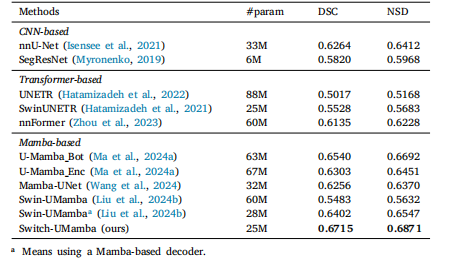

Table 2Results of instruments segmentation on the Endoscopy dataset. For a faircomparison, the Swin-UMamba results are reported without the benefit ofImageNet-based pre-training

表2 内窥镜数据集上的器械分割结果 为保证对比的公平性,所报告的Swin-UMamba模型结果未借助基于ImageNet的预训练(优势)。